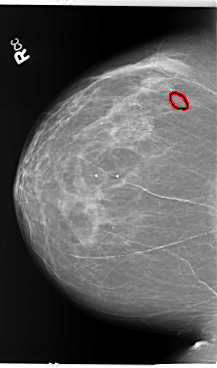

B_3141_1.RIGHT_CC

RIGHT_CC LINES 5880 PIXELS_PER_LINE 3472 BITS_PER_PIXEL 12 RESOLUTION 50 OVERLAY

FILE: B_3141_1.RIGHT_CC.OVERLAY

TOTAL_ABNORMALITIES 1

ABNORMALITY 1

LESION_TYPE CALCIFICATION TYPE PLEOMORPHIC DISTRIBUTION CLUSTERED

ASSESSMENT 4

SUBTLETY 3

PATHOLOGY BENIGN

TOTAL_OUTLINES 1

BOUNDARY